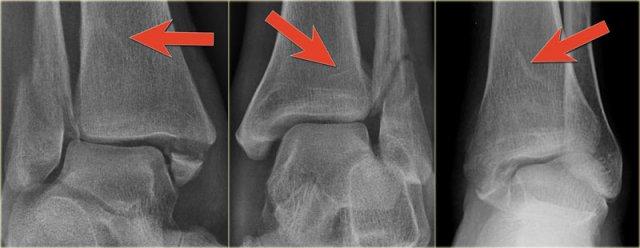

Đây là hình ảnh của một ca bệnh cực kỳ khó.

Bệnh nhân nữ bị bong gân cổ chân và đau cả hai bên trong và ngoài.

Bệnh nhân được bác sĩ đa khoa chuyển đến khoa Chẩn đoán Hình ảnh.

Kỹ thuật viên chụp các tư thế chuẩn gồm thẳng (AP), Mortise và nghiêng, sau đó trình bày cho bác sĩ X-quang, người đã khá băn khoăn khi đọc phim.

Hãy đọc hình ảnh trước, sau đó tiếp tục đọc phần giải thích.

Các dấu hiệu bao gồm:

-

Phù nề phần mềm cả hai bên trong và ngoài (mũi tên đỏ).

Đặc biệt, phù nề phía trong nên gợi ý khả năng chấn thương xoay ngoài – sấp (Weber C). - Đường thấu quang trên tư thế Mortise (mũi tên đen) và tư thế nghiêng. Dấu hiệu này nên gợi ý gãy tertius.

Bác sĩ X-quang quyết định chỉ định CT trước để xác định xem có thực sự có gãy tertius hay không.

Tiếp tục xem hình ảnh CT và bạn sẽ ngạc nhiên.

Hãy cuộn qua các lát cắt.

Thật đáng ngạc nhiên khi một mảnh tertius lớn như vậy lại rất khó nhìn thấy trên phim X-quang.

Cũng lưu ý phù nề phần mềm phía trong gợi ý đứt dây chằng bên trong (mũi tên).

Bạn có thể đoán được đây là loại chấn thương gì không?

Phù nề phần mềm phía trong và gãy tertius đều là dấu hiệu của chấn thương Weber C hoặc chấn thương xoay ngoài – sấp.

Do không thấy gãy xương mác trên phim X-quang cổ chân, phải có gãy xương mác cao.

Khi khám lâm sàng, có phù nề nhẹ phía trong và mặc dù bệnh nhân không than đau ở vùng cao hơn của cẳng chân, vẫn có điểm đau khi ấn vào xương mác.

Vị trí này được đánh dấu và phát hiện đường gãy.

Ca bệnh này minh họa tầm quan trọng của phù nề phần mềm phía trong cũng như dấu hiệu gãy tertius.

Theo phân loại Lauge Hansen, chúng ta có thể kết luận rằng bệnh nhân này đầu tiên bị đứt dây chằng bên trong (giai đoạn 1), tiếp theo là đứt dây chằng chày mác trước (giai đoạn 2), gãy xương mác cao (giai đoạn 3) và cuối cùng là bong mắt cá sau, tức là chấn thương xoay ngoài – sấp (PE) giai đoạn 4.

Trong phẫu thuật, cổ chân được xác định là không vững và vít cố định khớp chày mác đã được đặt vào.

Có chỉ định cố định gãy mắt cá sau vì mảnh gãy chiếm hơn 25% diện khớp của đầu dưới xương chày.